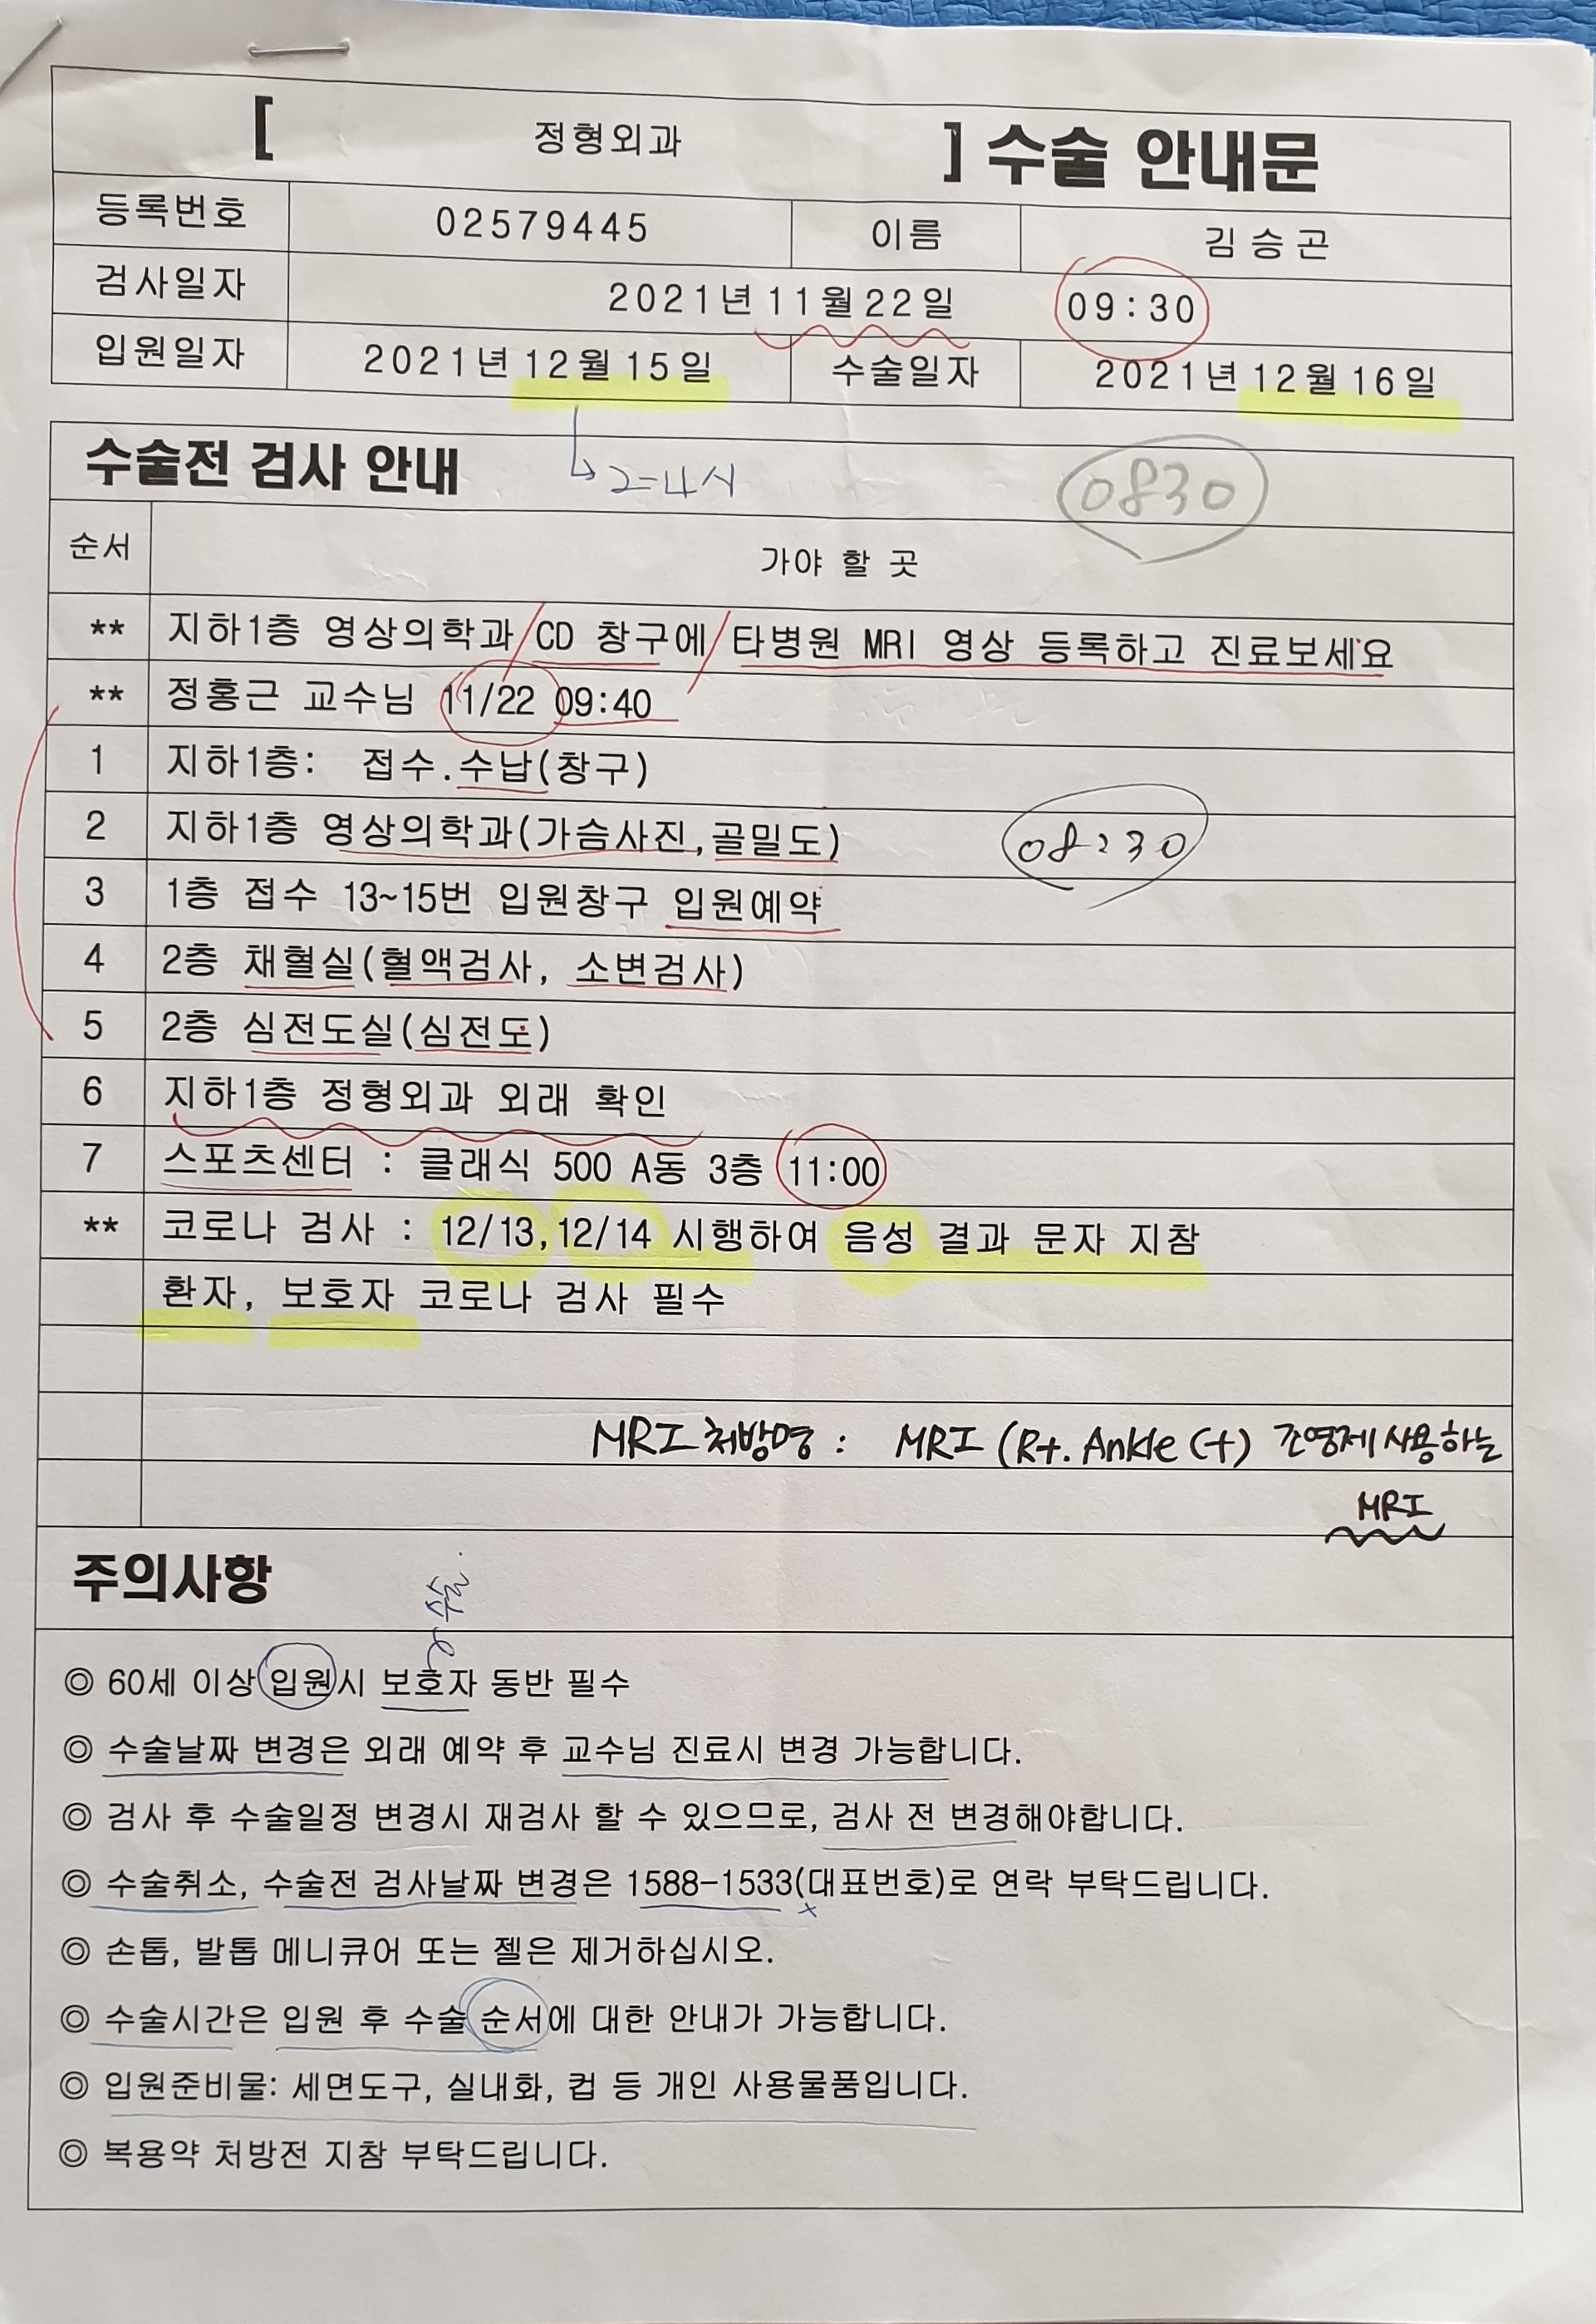

일정을 논의하는데 12월 15일 입원해서 16일 수술 하는걸로

그리고 다음 진료일을 11월 22일로 잡았는데 그날 MRI 를 다시 찍고 수술전 검사를 하는걸로 했다.

또 수술전 검사를 12일 하자고...

그러면서 수술전 진료일은 없다며 수납후 검사를 받으면 된다 한다.

11월 12일.............

16시까지 와서 수납후 검사를 받으라는 통보에 아마도 도착이 15시 30분쯤 되었지 싶다.

수납하는데 1,262,650원이다.

영상의학과에서 가슴사진과 골밀도 사진을

그리고 수납옆 창구에서 입원 예약을

또 채혈실에서 채혈및 소변 검사를

그리고 심전도 검사

영상의학과에서 17시 30분 예약 되어 있는 MRI검사를....

마치고 나오는데 18시 30분쯤 되었지 싶다.